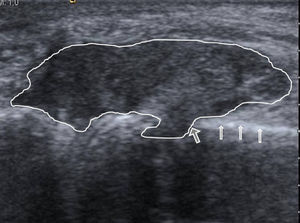

The ultrasound showed no effusion, but found a soft tissue injury, partially defined, and heterogeneous echotexture with hyperechoic areas. The tumor was in contact with the cortical bone of the metacarpal, which remained intact, except for an area where we observed a marked erosion, with a soft tissue lesion projecting into the medullary cavity (Fig. 1). Given the ultrasonography findings, X-rays were analyzed, confirming increased periarticular soft tissues, with very high density, accompanied by erosion of the metacarpal head, which as a hallmark had a sclerotic margin (Fig. 2). These sonographic and radiographic findings indicated periarticular tophi associated with bone erosion. The ultrasound-guided arthrocenthesis of the tophus showed a dense whitish material that under polarized light microscopy was identified as monosodium urate crystals (Fig. 3).

X-rays centered on the fifth metacarpophalangeal joint of both hands that allows for the assessment of the bone erosion comparatively and shows the sclerotic margin (arrows) with soft tissue augmentation and high density in the medial aspect of the right metacarpal head. There was no involvement of the joint space.